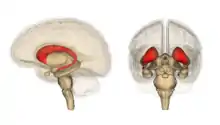

Brain structures

The leading experimental technique for studying proactive interference in the brain is the “recent-probes” task. Initially, this is when participants must commit a set of items to memory. They then ask them to recall a specific item. Assessing them is shown by a probe.[10] Thus, using recent-probes task and fMRIs, the brain mechanisms involved in resolving proactive interference identify as the ventrolateral prefrontal cortex and the left anterior prefrontal cortex.[11]

Retroactive Interference has been localized to the left anterior ventral prefrontal cortex by magnetoencephalography (MEG) studies investigating Retroactive Interference and working memory in elderly adults.[23] The study found that adults 55–67 years of age showed less magnetic activity in their prefrontal cortices than the control group. Executive control mechanisms are located in the frontal cortex and deficits in working memory show changes in the functioning of this brain area.[23]